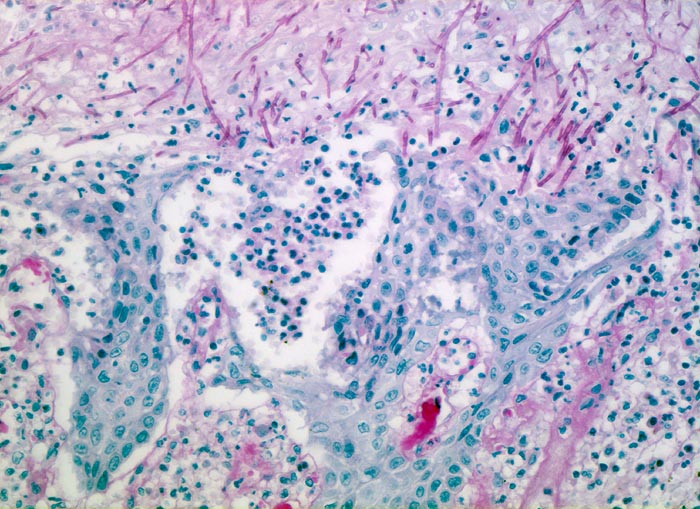

Soorösophagitis

Entzündung infektiös

Oesophagus

Erodierte Schleimhaut mit regeneratorischen Epithelatypien (vergrösserte, leicht polymorphe Kerne mit vergröbertem Chromatin, wenig Zytoplasma). Zwischen den Epithelinseln dichte Infiltrate neutrophiler Granulozyten. PAS positive Soorpseudohyphen infiltrieren das erodierte Epithel.

Mann, 75 Jahre, mit bekanntem multiplen Myelom. Autopisepräparat. Progrediente Dysphagie.

Histologie

200